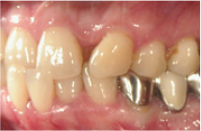

治療例1

| 初診時年齢 | 56歳 |

|---|---|

| 主訴 | 受け口が気になる |

| 診断名 | 叢生を伴う下顎前突 |

| 治療に用いた装置 | リンガルブラケット矯正装置 |

| 抜歯部位 | 非抜歯 |

| 治療期間 | 2年6ヶ月 |

| 費用の目安 | 1,250,000円~ |

治療前

治療後